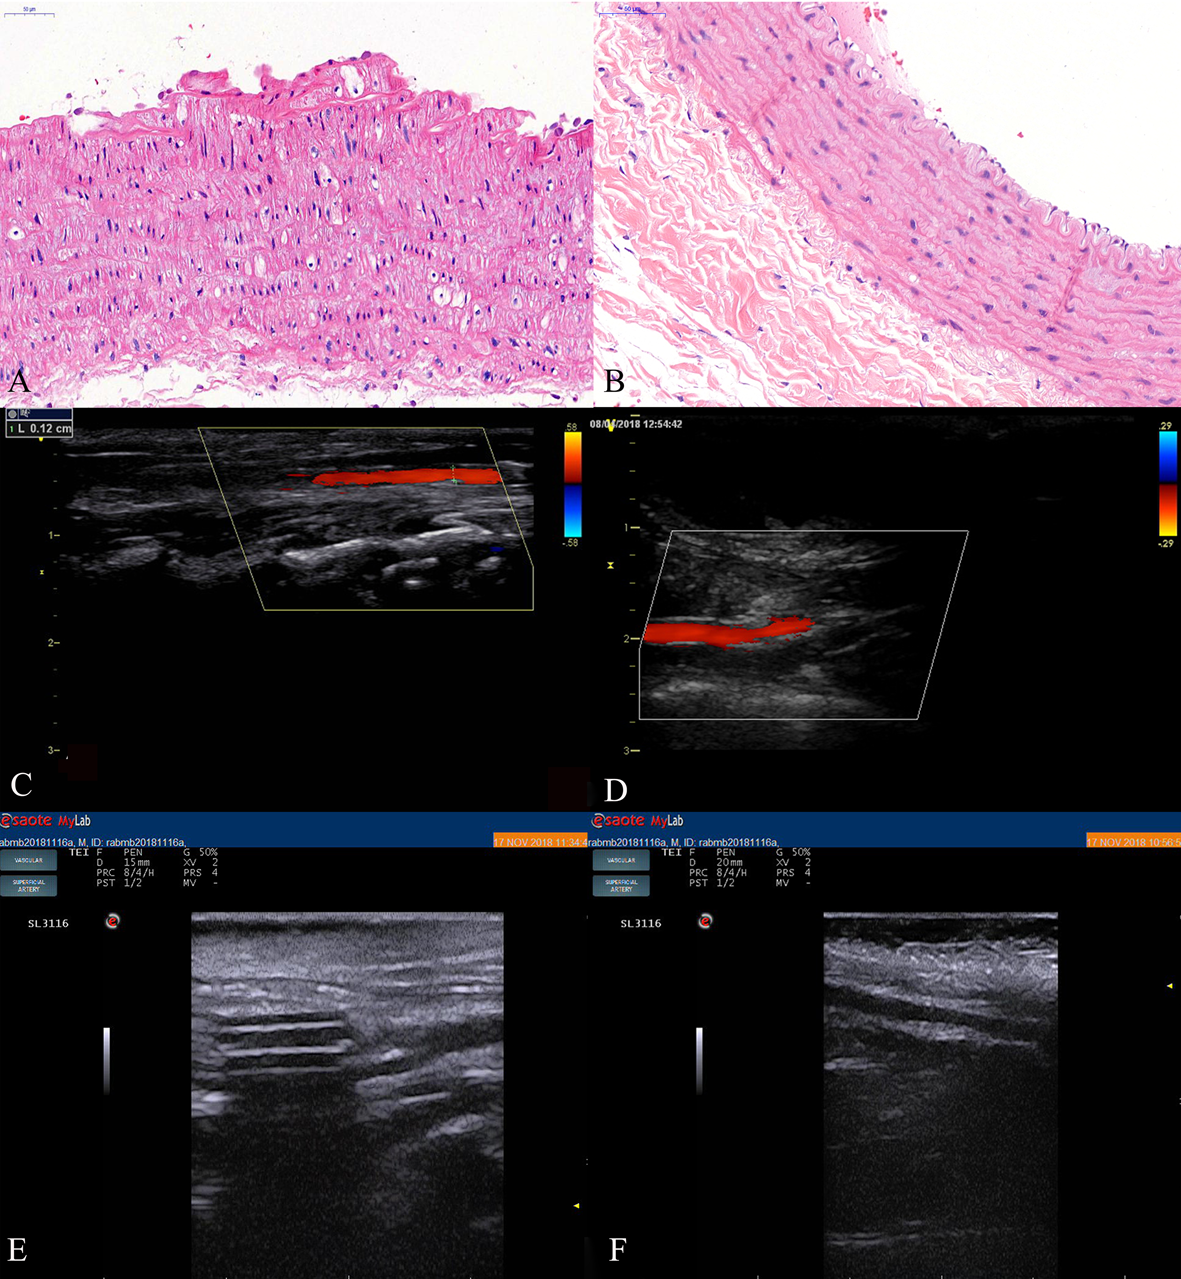

In order to verify the presence of atherosclerotic plaques, HE staining and contrast-enhanced ultrasound (CEUS) examination were used. In the experimental groups, foam cells were observed under the lesioned intima. The surface fibrous cap structure was broken, the elastic fibers were damaged and thinned, the thickess of media was increased with augmanted smooth muscle cells number and presence of foamy cells, and plaques were observed protruding into the lumen (Fig. 2A). The rabbit endothelial cells in the control group were intact (Fig. 2B).

Fig. 2.Formation of vulnerable plaque in rabbit atherosclerosis. (A) HE

staining of carotid atherosclerotic plaque in rabbits. (B) HE staining of carotid

artery in rabbits of control group (400

CEUS showed that the carotid artery

intima-media thickness (IMT) was thickened 0.03 mm, and the color Doppler flow

signal was well-filled at week 4. At week 8, the carotid artery IMT was thickened

more, and some rabbits had small plaques protruding into the lumen. Color Doppler

flow imaging (CDFI) showed a filling defect of blood flow at the plaque at the

week 8 and week 12, and the diameter stenosis rate was less than 30% (Fig. 2C,D).

Compared with the preoperative findings, the difference was statistically

significant (t = 24.96, p